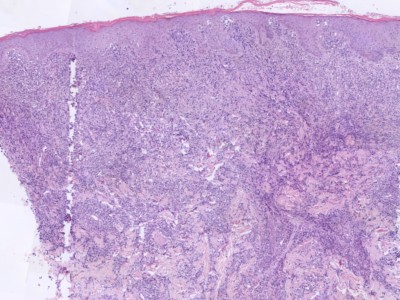

Primair cutaan

grootcellig B-cellymfoom van het beentypeDit type cutaan

lymfoom komt vooral voor bij oudere patiënten (>70 jaar). Klinisch ziet

men één

of meerdere paarsrode tumoren op één of beide (onder)benen. Bij circa 10%

elders op het lichaam. Histologie: diffuus infiltraat van centroblasten en immunoblasten, bcl-2, Mum-1 en Fox-P1

positief. Zie ook de

ingescande PA-coupe van de

afdeling pathologie van de University of